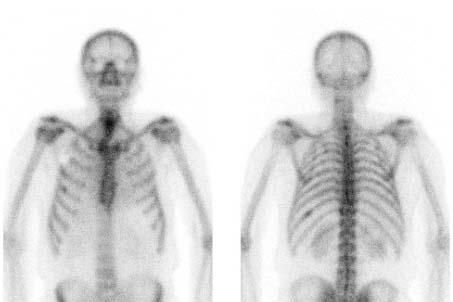

Knochen-/ Skelettszintigrafie: Untersuchung des Knochenstoffwechsels. Hierzu wird eine schwach strahlende Substanz in eine Armvene injiziert und später wird deren Verteilung im Körper gemessen. Nebenwirkungen treten dabei nicht oder sehr selten auf.

Meist werden bereits während oder kurz nach der Injektion erste Aufnahmen angefertigt. Anschließend sollten Sie bis zum Beginn der Aufnahmen nach 2-3 Stunden etwa 1 1/2 l Flüssigkeit, z.B. Wasser, Tee oder Saft trinken. Essen dürfen Sie ohne Einschränkung.

Die eigentliche Aufnahmen werden durchgeführt, nachdem sich die Substanz im Körper verteilt hat. Dies dauert 2-3 Stunden. Während der Aufnahme liegen Sie auf einer Liege und die Gammakamera fährt über Sie hinweg. Eventuell sind anschließend noch Schichtaufnahmen (SPECT-Aufnahmen) notwendig.